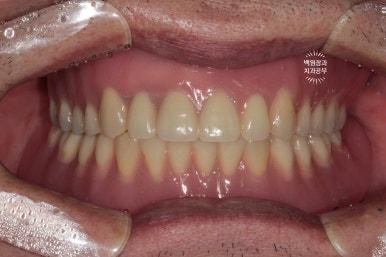

이렇게 완성된 위아래 틀니를 착용하신 상태입니다.!

임플란트보다 틀니가 나은점은 분홍색 잇몸부분을 갖고 있기 때문에, 생각보다 예뻐보인다는 것..

덕분에 10년은 젊어보이시는 외모를 되찾으셨습니다.!

Before & After!!

임플란트 틀니. 잘만 사용하면 전체 임플란트 못지않게 효율적인 치료입니다!

그리고 퀄리티가 상당히 좋은 훌륭한 치료입니다.